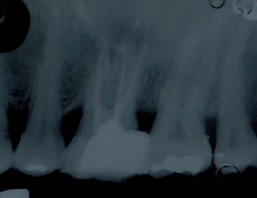

Capita spesso di incontrare denti già devitalizzati in maniera impropria che necessitano, seppur asintomatici, di essere ritrattati per evitare che i granulomi infetti visibili radiograficamente si evolvano riassorbendo tutto l’osso sottostante.

Un adeguata endondonzia serve per salvare quei denti che altrimenti sarebbero destinati ad essere estratti. Quando un dente viene devitalizzato viene privato della sua irrorazione sanguigna e del nutrimento, rendendo la sua struttura più “vetrosa” quindi più fragile e soggetta a fratture. Per questo motivo è consigliabile nella maggior parte dei casi capsulare i denti una volta che hanno perso la loro vitalità.